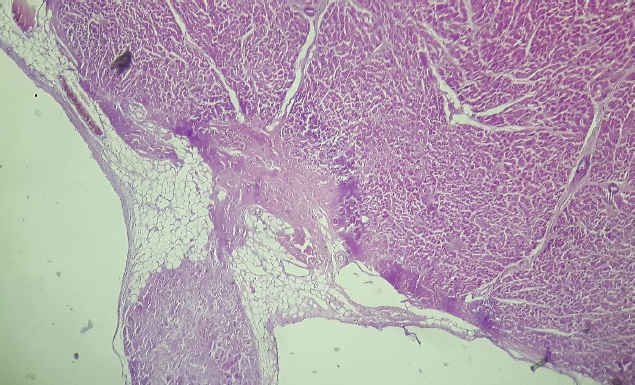

After 24 Holter monitoring, the patient died suddenly during physical activity. Permission for conducting necropsy was obtained from the animal owners. Postmortem examination showed marked cardiomegaly (heart weight bigger than 13 g/kg body weight). No lung edema, pleural effusion or ascites were observed. The heart was explanted and preserved in 10% formalin and then sent for examination to the pathology service of the Hospital Santojani (Buenos Aires), where fragments from both ventricles and the septum were processed with the routine technique to make paraffin-embedded blocks. 4 μm thick sections were cut and stained with hematoxylin-eosin (H&E). Adipose and fibroadipose replacement of the right ventricle free wall of up to 50% of its thickness was observed. These lesions had a predominantly subepicardial distribution. Subepicardial fibroadipose replacement of the left ventricle with involvement of the septum was also observed (Fig. 3). In addition, adipose tissue was also observed in the left ventricle, affecting the base of implantation of the papillary muscles at the septum (Fig. 4). In areas of the left ventricle, co-existence of perivascular fibrosis, myocardial fibrosis suggestive of previous necrosis, and interstitial fibrosis were detected (Fig. 5). In addition, wavy fibers in the myocardium in both ventricles were observed. Clusters of myocardial fibers were also observed within all areas of adipose tissue deposition.

Fig. 3. Septum, basal level of the left ventricular side (H&E, 100×). Histopathological image showing subendocardial adipose tissue deposition with fibrosis and hyalinization.

Fig. 4. Base of the left ventricle papillary muscle (H&E, 100×). Histopathological image showing presence of adipose tissue at the base of the papillary muscle.